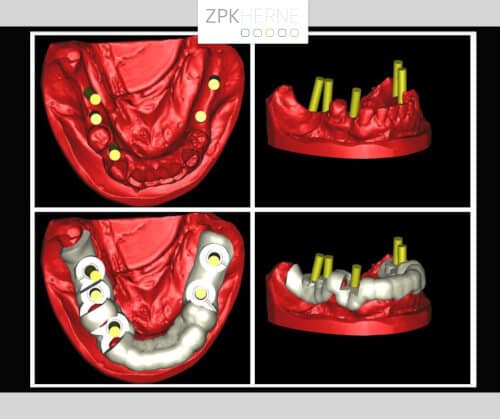

Nach der gründlichen Anamnese werden aktuelle 3D-Aufnahmen der Gebisssituation erstellt. Dabei kommt das Team um Herrn Dr. Mintert zu den folgenden Ergebnissen und Handlungsschritten:

Zur Vorbereitung auf den Tag der Operation wird eine Bohrschablone auf Basis der DVT-Planung angefertigt. So werden die genauen Positionen der einzelnen OP-Schritte festgehalten, damit keine Nervverletzung entsteht. Der chirurgische Eingriff findet unter Vollnarkose statt, hier ist genaueste Konzentration gefragt. Zunächst wird das OP-Gebiet gründlich gereinigt, damit keine Bakterien in die Wunde gelangen. Nun Schnittführung auf den Kieferkämmen: Das Gewebe wird vorsichtig abgelöst und der Knochen freigelegt. Die Bohrschablone wird anprobiert und die Bohrungen für die Implantate Schritt für Schritt durchgeführt. Die Implantate werden nach und nach maschinell eingebracht und radiologisch kontrolliert. Währenddessen wird eine mit Blutplättchen und Wachstumsfaktoren angereicherte Fibrinmembran (LPRF) hergestellt, indem eine gewisse Menge Blut des Patienten zentrifugiert wird. Dies dient der besseren Wundheilung und ist unter dem Begriff „Eigenbluttherapie“ als besonders schonende und effiziente Behandlungsmethode bekannt.